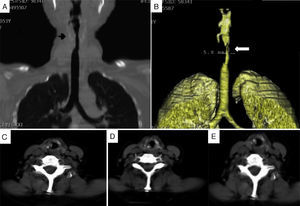

Patient no. 2A 64-year-old woman who had been diagnosed with GPA at the age of 57 years. At the age of 59, she presented with dyspnea and stridor. Computed tomography (CT) of larynx and trachea revealed a granulomatous lesion obstructing the tracheal lumen (Fig. 1). Bronchoscopy disclosed an obstruction of 75% in subglottis, and tracheal dilatation and tracheostomy were performed. Two months later, the patient presented with restenosis of 85% requiring tracheal dilatation, and 2 weeks after that, SGS of 50% was detected, and tracheoplasty was performed using the technique of Grillo and Pearson. The patient required repeat dilatation 18 months later due to SGS of 80%. Fifteen months after that last dilatation, bronchoscopy revealed SGS of 30%, and resolution of dyspnea and stridor. As restenosis did not occur over the following 7 months, decannulation was possible.

Patient no. 3A 44-year-old man had been diagnosed with GPA at the age of 39 years. Two months after the diagnosis, he presented with laryngeal stridor, dyspnea, foreign body sensation in his larynx and dysphonia. Fiberoptic laryngoscopy revealed SGS of 20% with systemic activity (BVAS score of 23). He was treated with 3 doses of 1g/day of methylprednisolone and intravenous cyclophosphamide; the systemic manifestations remitted, but his dysphonia, stridor and dyspnea progressed. One month later, CT revealed concentric circumferential thickening that partially obstructed the tracheal lumen (Fig. 2 A and B). Bronchoscopy showed SGS of 70%, with erythematous laryngeal structures. He received 3 doses of 1g/day of methylprednisolone and underwent tracheal dilatation. Subsequently, the clinical course was satisfactory, with remission of the stridor and improvement in the symptoms. However, 7 days later, his symptoms recurred, with 100% restenosis (Fig. 2C and D), which required emergency tracheostomy.

Computed tomography of larynx and trachea in patient no. 3. (A and B) Axial images showing the subglottic stenosis with concentric circumferential thickening of the mucosa (*) partially obstructing the tracheal lumen. (C) Subglottic stenosis (arrow). (D) Volumetric reconstruction of subglottic stenosis (arrow).